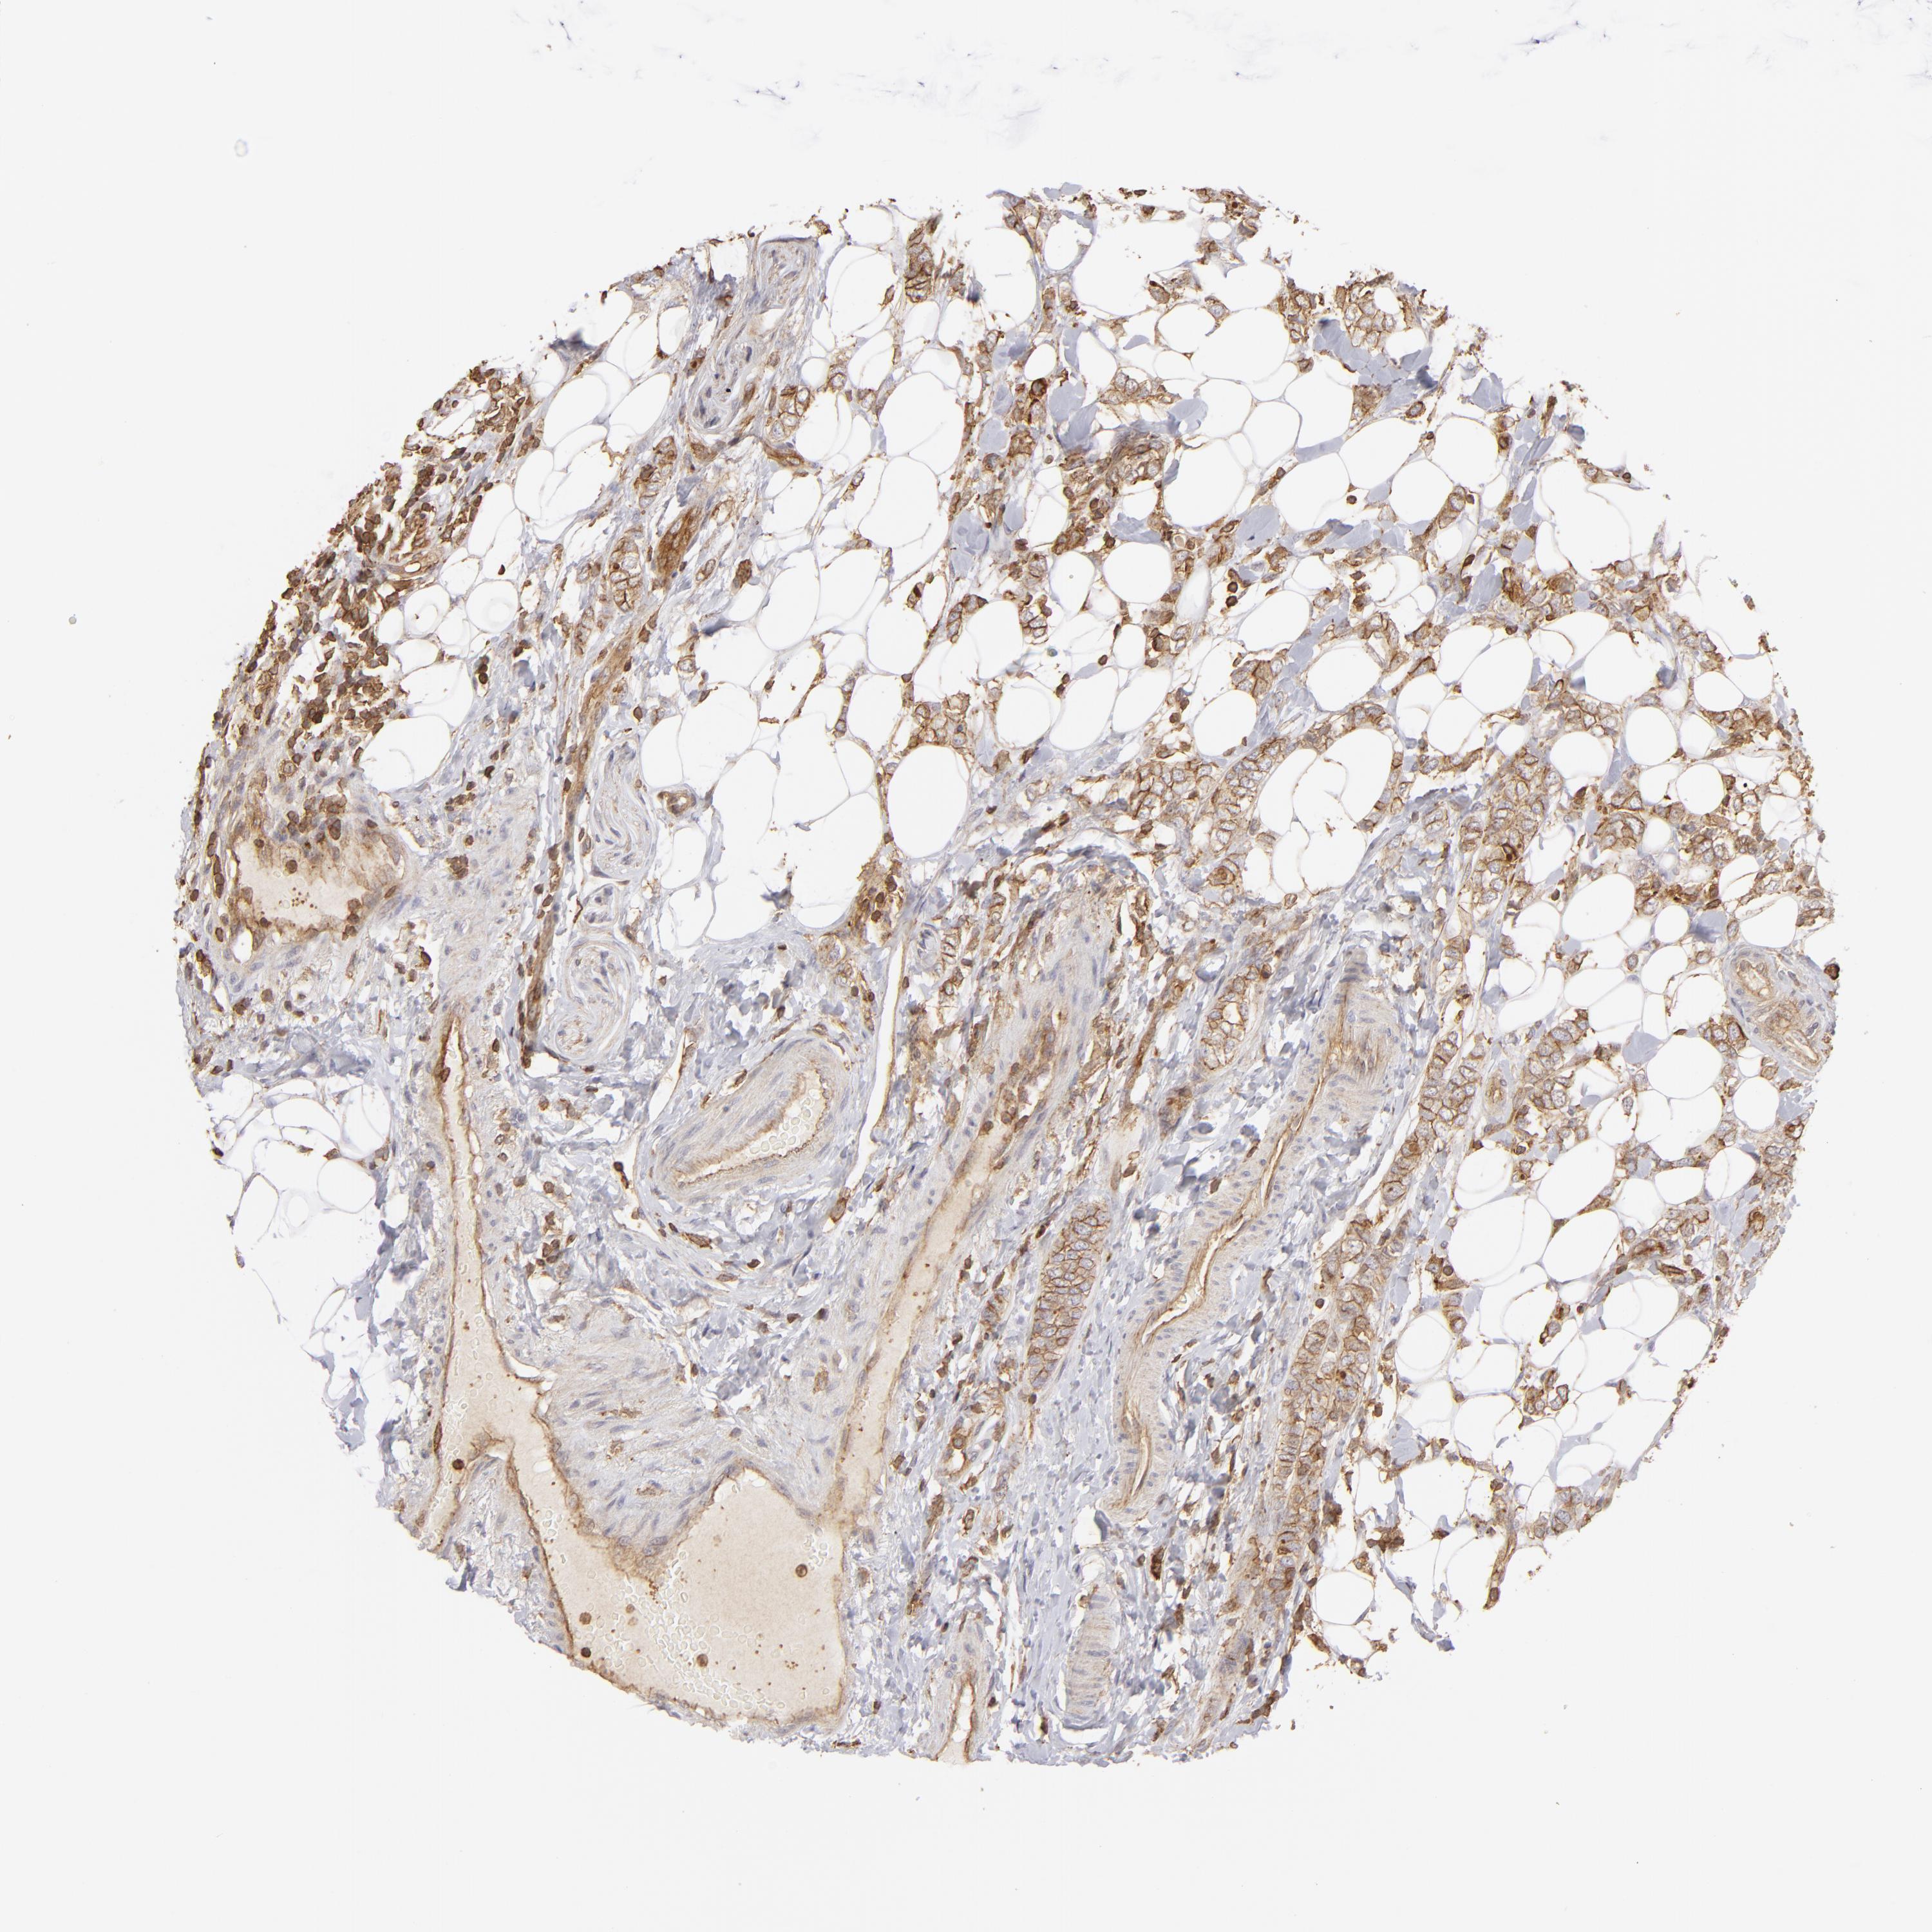

BRCA TCGA BRCA VALIDATION PROTEIN EXPRESSION

ANTIBODIES

AND

VALIDATION